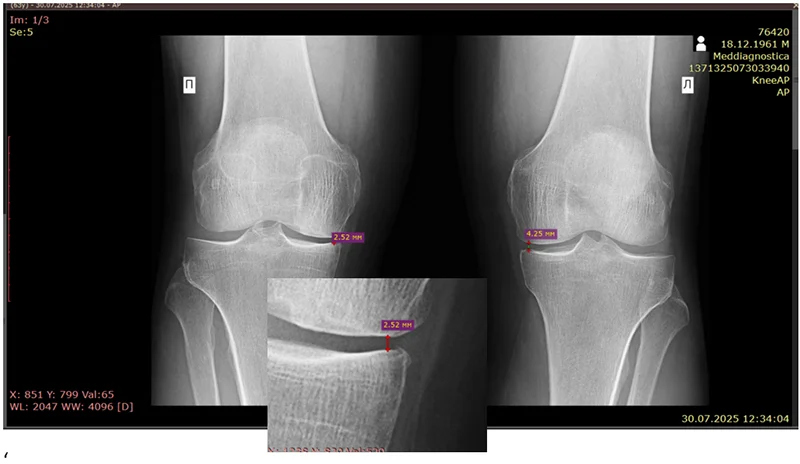

На рентгені, що далі – стан суглобової щілини до лікування (на 30.07.2025):

В наведеному випадку зменшення висоти суглобової щілини в коліні порівняно з здоровим суглобом свідчило про розвиток артрозу.

У нашого пацієнта була майже 3-тя стадія артрозу правого коліна – стан, який часто швидко переходить і переходить в 4-ту стадію (коли без ендопротезування не обійтися).